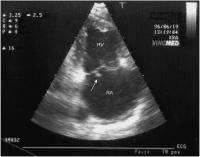

Flottierender Thrombus

Abbildung 4: Flottierender Thrombus rechtes Atrium (subkostaler Querschnitt)